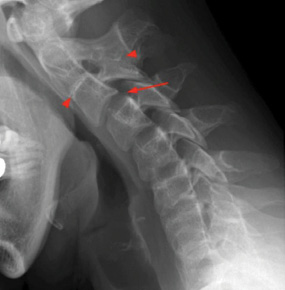

A 72-year-old female patient arrived at the Emergency Department (ED) of the Hospital of Lithuanian University of Health Sciences Kaunas Clinics. The patient presented with complaints of speech disturbances, neck pain, numbness in her hands, and difficulty climbing stairs. The symptoms had persisted for over two days without improvement. Based on her medical history, in April 2023, the patient had been treated for a severe episode of neck pain, and a neck X-ray was performed, revealing congenital partial fusion of the C2–C3 vertebrae, as indicated by arrows in Figure 1.

There is growing evidence suggesting a possible correlation between Klippel-Feil Syndrome (KFS) and the development of PRES. KFS is a congenital syndrome resulting from the fusion of at least two cervical vertebrae. Despite this clinical and genetic heterogeneity, it has been reported that the most frequent cervical fusions occur at C5–C6 and C2–C3. However, patients with Klippel-Feil syndrome are often asymptomatic; nevertheless, they may develop a number of spontaneous neurologic sequelae as a result of their bony anomalies. KFS is often incidentally detected on cervical imaging following a traumatic event. Its clinical presentation can vary widely, ranging from asymptomatic cases to severe spinal fusion and accompanying visceral abnormalities, necessitating a multidisciplinary approach. Genetic mutations linked to KFS involve chromosomes X, 12, 17, and 22. The syndrome manifests with restricted cervical spine mobility, a shortened neck, and a low posterior hairline. Complications such as central canal stenosis may also arise. In some cases, KFS is associated with multisystem involvement, including cardiac, renal, and auditory abnormalities [4,5,6].